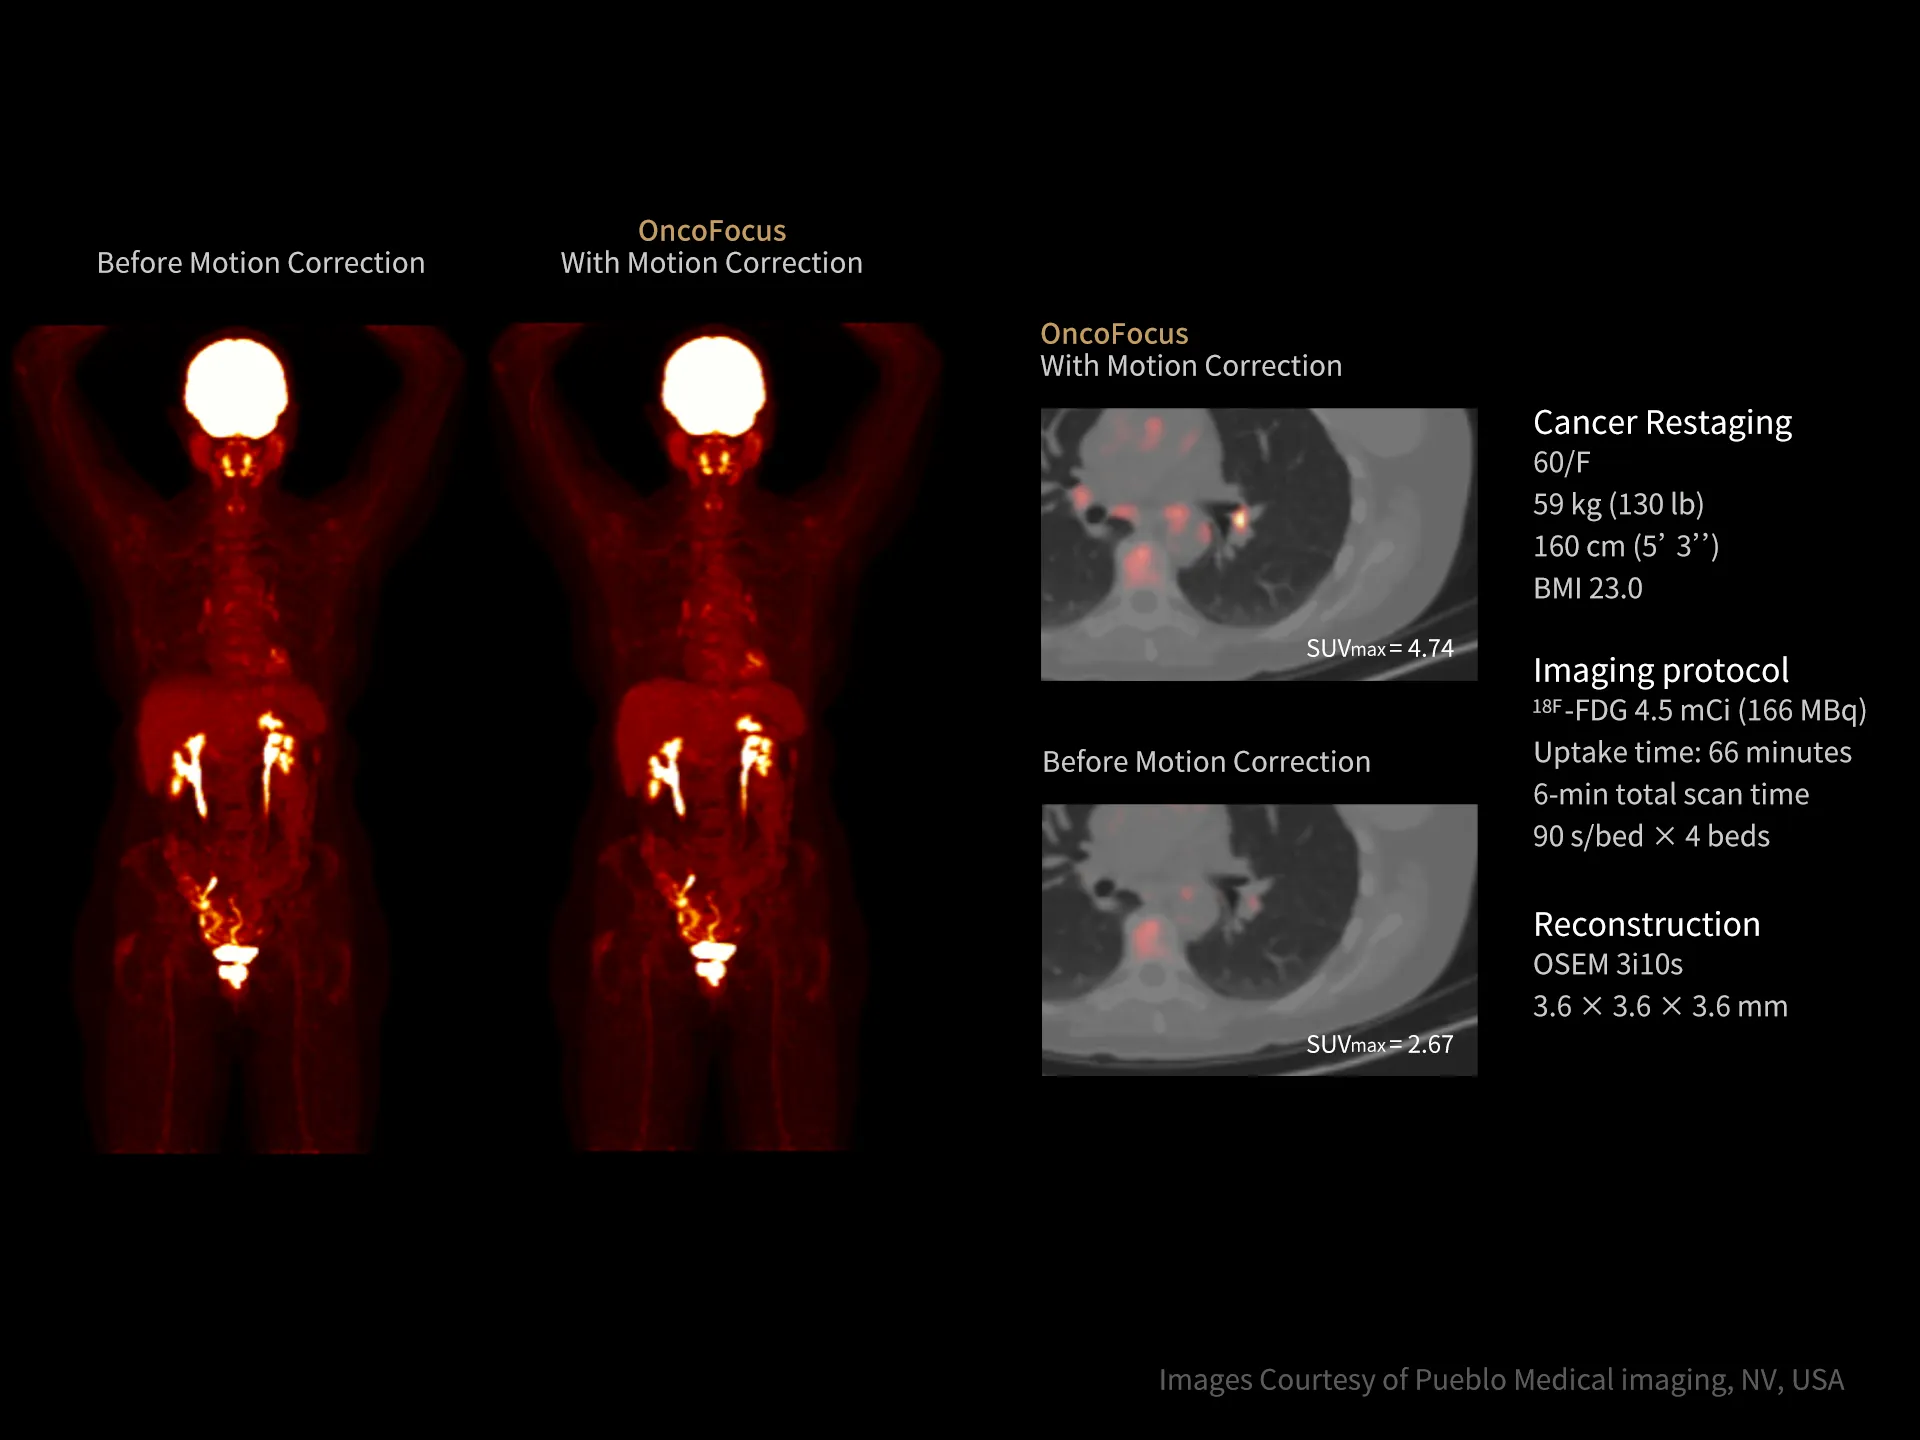

uMI Panvivo is a high performance PET/CT platform that moves state-of-the-art innovative advancement to clinical reality. It advances diagnostic precision with industry-leading NEMA spatial resolution of 2.9mm and time of fight (TOF) timing resolution of 219 picosecond (ps), while it’s air-cooled compact design make it more accessible to all. The human-centric design and fully AI-empowered workflow of uMI Panvivo deliver care to every patient while keeping the user in mind. Built on its scalable platform, uMI Panvivo’s powerful design builds the bridge toward long-term and sustainable success.

Driven by precision medicine and personalized care, uMI Panvivo offers the top-tier performance based on state-of-the-art detector technology and highly integrated system for better diagnostic confidence and capabilities.

Top-tier Performance

Exceptional NEMA spatial resolution delivered by the finest crystal size of 2.76 mm in the industry.

Leading TOF resolution that boosts small lesion detectability and clarity.

High effective sensitivity that benefits from TOF gain leverages better diagnostic accuracy under low dose usage and fast scan time.